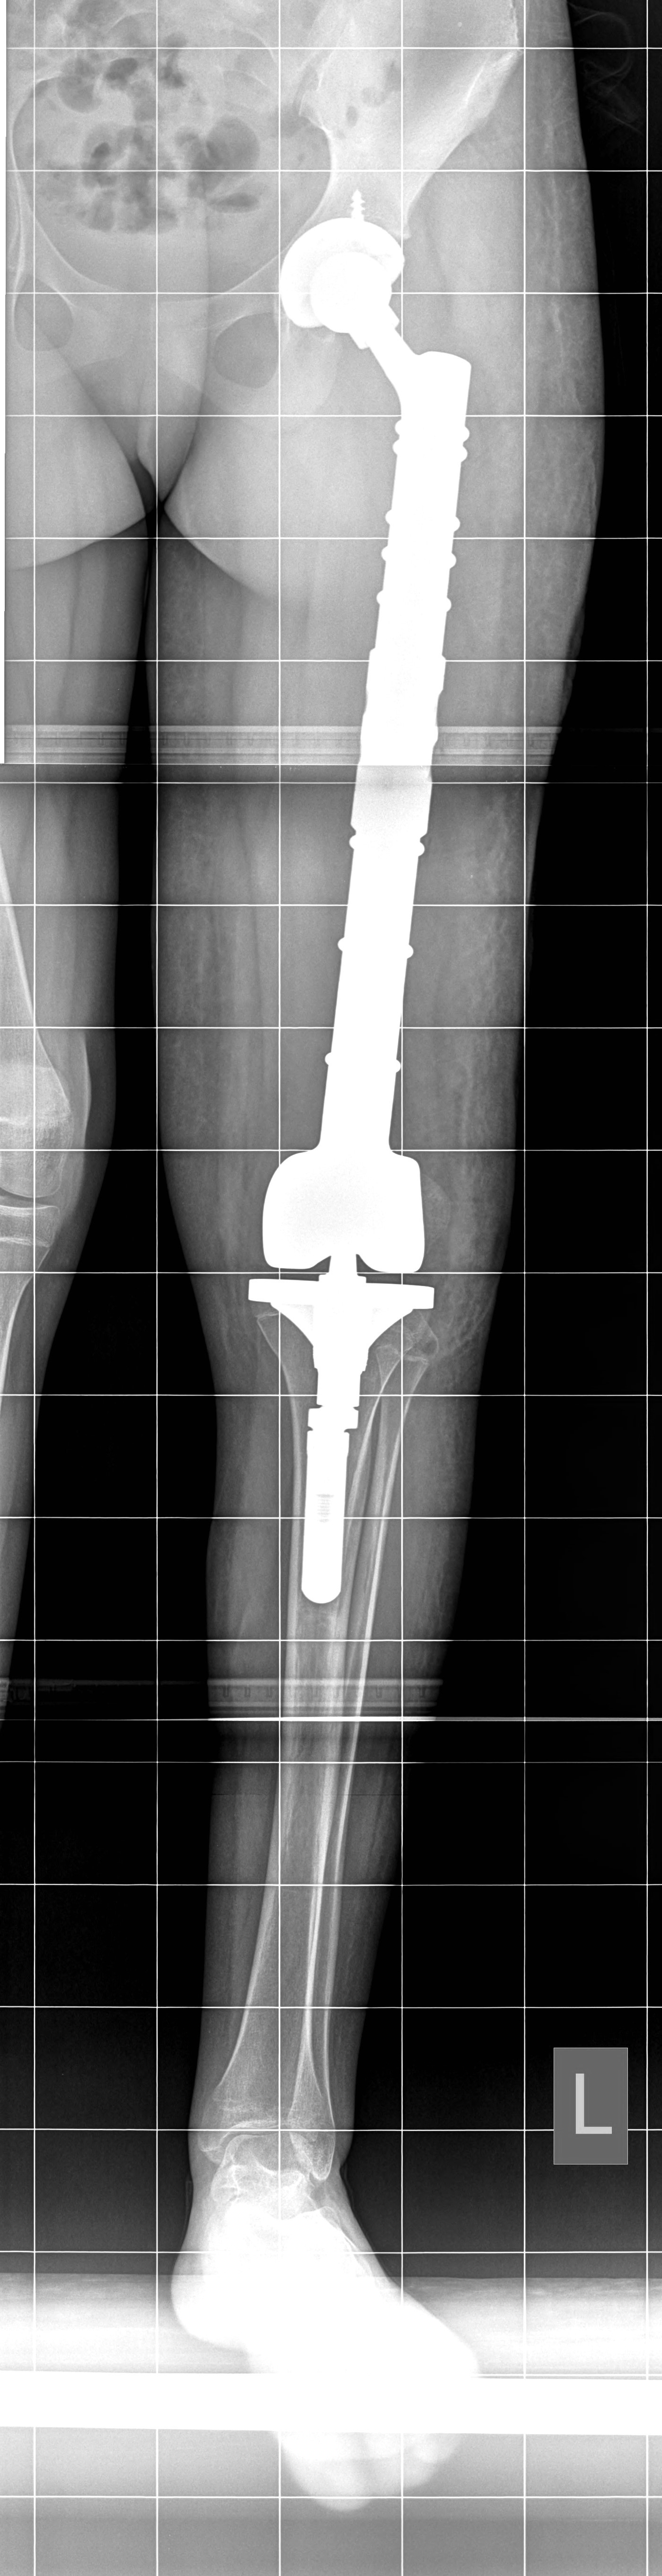

Две седмици след уникална операция в Университетската специализирана болница за активно лечение по ортопедия “Проф. Бойчо Бойчев” в Горна баня 13-годишната Райна Т. от Пловдивско може отново да ходи с двата си крака. Момичето постъпва в ортопедичната болница със страховитата диагноза Сарком на Юинг, обхващащ лявото бедро по цялото протежение. След проведена предоперативна химиотерапия в Детската онкохематология в Пловдив екип на Клиниката по ортопедия извършва премахване на тумора с цялата бедрена кост и заместване на дефекта с модулна мега-протеза, включваща бедрено стебло, ендопротези на тазобедрената и коленната стави.

„Отстранихме цялата бедрена кост и извършихме реконструкция с туморна модулна ендопротеза, изработена в Германия, обяснява д-р Патриков. Протезата е бутикова, поръчана и изработена, съобразно размерите на костите на пациентката. Тази модулност позволява и по-късно във времето при необходимост да се подменят модулите. Защото пациентката е на 13 години и се предполага, че има още 1-2 години растеж на костта. Така че, ако в процеса на израстване оперираният крак изостане по дължина от другия, ще има възможност да бъде уеднаквен с подмяна на един от поставените по средата модули.